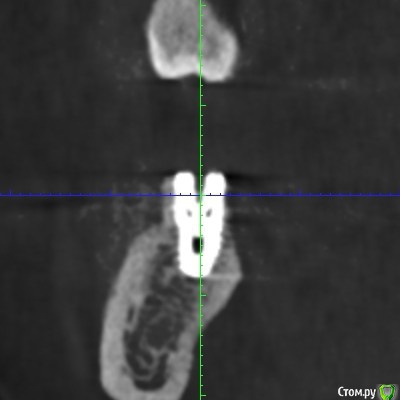

Irina_S Опубликовано 6 января, 2018 Поделиться Опубликовано 6 января, 2018 Здравствуйте, уважаемые спеицалисты! С наступившим вас Новым годом!!! В конце августа были установлены три имплантата Xive - 36, 46, 47. Одновременно с установкой выпиливалась кость и прикручивалась винтиками в те места, где по мнению хирурга её не хватало. В середине октября сквозь десну с язычной стороны стали просматриваться верхушки имплантатов 36 и 46. Во время периодических осмотров врач говорил, что всё в порядке.В декабре пришло время установки формирователей десны. Установивший имплантаты хирург стал работать в другой клинике. Он пригласил на осмотр, сказал, что надо будет добавить десну в области 36 и 46, взяв кусочки с нёба, а с самими имплантатами всё хорошо, можно одновременно с пластикой десны ставить формирователи и через 2-3 недели отправляться к ортопеду.Следуя логике сохранения гарантии на установку имплантатов, которую даёт не врач, а клиника, я пошла к другому хирургу в ту клинику, где устанавливались имплантаты. Он посмотрел на выступающие верзушки имплантатов, причём 36 успел к этому времени уже прорвать десну. Посмотрел КТ и сказал, что предварительно видит проблемы и помимо пластики десны может понадобиться переустановка имплантатов. Самый проблемный, по его мнению, 46, а 36 - под вопросом. Сказал, что окончательное решение можно будет принять только после разрезания десны, чтобы увидеть фактическую ситуацию. Причём переустановка - по гарантии, и она будет делаться сразу - выкручивается старый имплантат и ставится новый, тоньше (3,8мм вместо 4,5мм) и длиннее. Соответственно, в этом случае снова ждать 3-4 месяца, и только после этого ставить формирователи. Присутствовавший на консультации ортопед был полностью с ним согласен и сказал, что на имплантаты в таком состоянии, как он их видит на КТ, он коронки ставить не будет. Аргументировалось тем, что кости в принципе достаточно, но имплантаты надо было устанавливать глубже, а так, как сейчас, они протянут максимум 3-4 года, а потом расшатаются и выпадут. Клиника даёт гарантию 10 лет, поэтому они считают, что нужно хорошо установить изначально.На месяц раньше ставились имплантаты в верхнюю челюсть, с ними всё хорошо. Но, рассматривая проекции КТ, я вижу обширные тёмные области в районе всех имплантатов как дефект засветки при формировании КТ. В связи с чем вопрос: может ли картина на КТ с отсутствием видимой костной ткани происходить из-за самого оборудования, на котором делается КТ, и не совсем соответствовать действительности? Иначе, есть ли шанс, что при вскрытии десны окажется, что с расположением импллантатов всё в порядке (как и уверяет "сбежавший" их этой клиники хирург), а альтернативное мнение связано в некотором роде с желанием опозорить уволившегося сотрудника и удержать пациента у себя, ведь потом предстоит большая ортопедическая работа? И ещё один вопрос: чего мог категорически не принимать ортопед, говоря, что в подобных случаях он всегда отправляет к хирургу, если заведомо было известно, что недостающая десна в любом случае будет наращиваться?С имплантатом 47 ситуация, вроде бы, не такая критическая. Это на самом деле так? Ссылка на комментарий

колесников Опубликовано 6 января, 2018 Поделиться Опубликовано 6 января, 2018 С десной однозначно предстоит поработать. Импланты расположены несколько язычно,что может быть проблематично. Ссылка на комментарий

колесников Опубликовано 6 января, 2018 Поделиться Опубликовано 6 января, 2018 Сколько врачей,столько и клинических подходов. Я бы переустановил нижние импланты заменив ксайв на Штрауман тл, плюс увеличил объём мягких тканей по гребню.Это ,как говорится ,обойтись малой кровью с благоприятным прогнозом. Если оставлять этот ксайв,то только пластики десны не достаточно,придётся перекрывать их костным материалом с мембраной и позднее Увеличить объём мягких тканей. Все бы ничего,но меня смущает язычное положение платформ имплантов и их уровень относительно соседних зубов. Это лично моё мнение,оно может отличаться от мнений коллег. Ссылка на комментарий

колесников Опубликовано 7 января, 2018 Поделиться Опубликовано 7 января, 2018 Анкилос отличный имплант,в прямом и переносном. Надо соблюсти ряд условий ,линейка размеров несколько ограничена,а заглубить желательно мм на 3,пройдёт ли вашем случае анкилос надо просчитать и как будут выглядеть коронки тоже вопрос. Штрауман тл имеет полированную шейку и может располагаться в мягких тканях ,другими словами его заглублять не надо в ваших ограниченных условиях и платформа будет максимально приближена к естественному уровню. Ссылка на комментарий